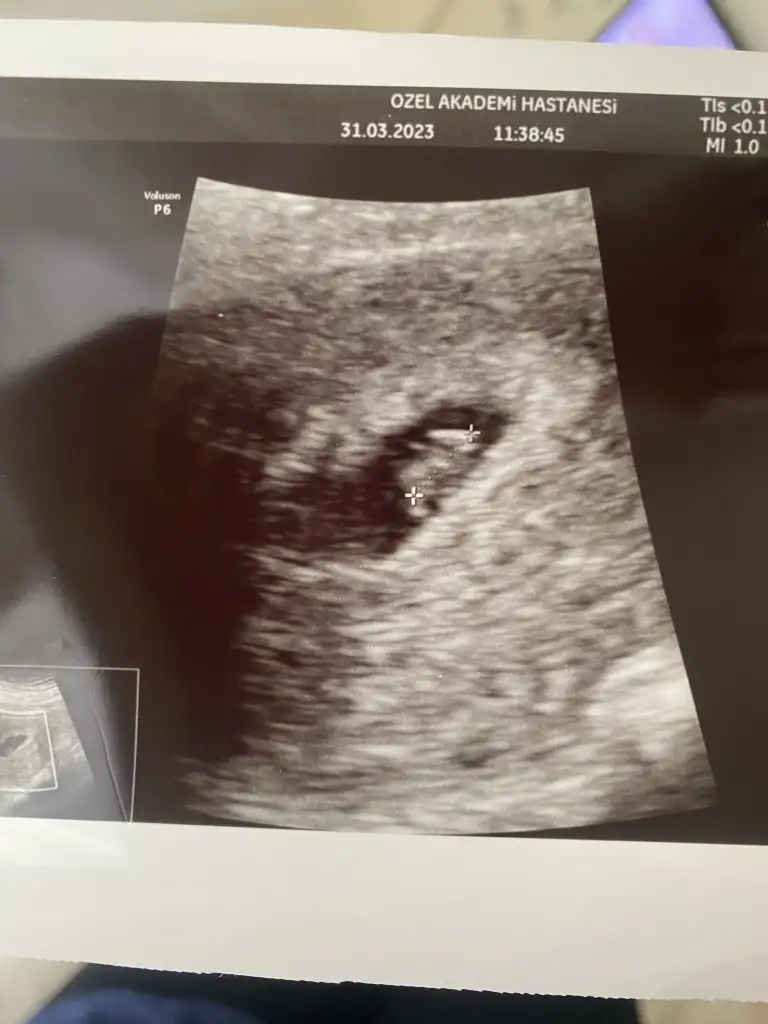

Merhaba hayırlı olsunKızlar merhaba,, ben de Kasım annesi olacağım inşallah. Dün ilk kez kontrole gittik karnımdan baktı kese göründü. Beta hcg 10. 000 üzerinde. Yerleşme kanamasından beri ara çok açık kahve lekelenmeler oluyor. Daha önce bir düşük yaptım korkuyorum. Sadece kese göründüğünde progestan veriyor mu doktorlar?

Karındanse eğer sanırım kız ama emin değilimkeseye göre tahmin yapan birileri vardıııı 7+5